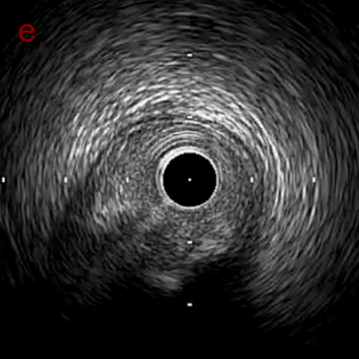

IVUS after OAS low speed 3回

IVUS imaging after low speed 3回

OAS low speedによる引きのsandingを3回行いIVUSを確認するとa-cでは心筋側側へのOASによる良好なbias変化と、それに伴いdの健常側への危険なbias変化を認めた。

そのためcでIVUSマーキングを行い、その点より引きで赤線のpinpoint OAS high speedを行い、dに関してはinjury回避のためにOASを当てない方針とした。